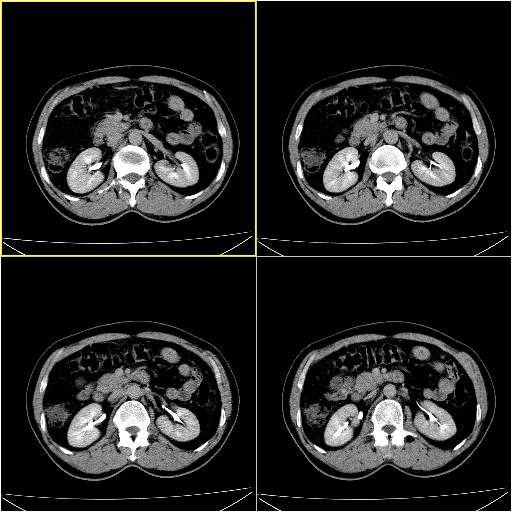

男性,54岁,皮肤黄染,搔痒一周余.b超示肝左叶回声异常.初步诊断1胆总管下段结石2胆囊结石伴慢性胆囊炎请各位战友帮忙看一下肝脏多发低密度如何解释恰当.增强效果不是很好.请大家见谅.

胆总管及肝内胆管扩张,考虑是结石!但,肝内的低密度区增强不明,可能是肝ca,因为肝ca在增强时呈快进快出.另年胆总管扩张原因,可以考虑一下是不是,胆管ca.再次要考虑肝内的低密度是否为海绵状血管瘤所致!

首先,胆总管下端结石梗阻伴肝内胆管扩张可确定。

另外,肝八段低密度占位,呈多灶性,考虑肝脓肿或肝癌可能,(图像质量欠佳)建议进一步检查。

既然做了增强,为什么光提供延时期片子,肝动静脉期肝右叶前下段病灶增强如何?另外胆囊壁增厚,欠规整,内密度不均,与肝右叶病灶分界不清,增强表现怎样?肝内胆管轻度扩张,胆总管扩张,但未见明显结石影,也应提供增强早期图像才好鉴别扩张原因。片子较清,但不够完整,暂考虑1.胆囊癌肝局部浸润,或肝癌胆囊侵犯,2.胆总管下端或胰头钩突部占位。总之本人看不明白,请高手画图指示,先谢了!

由于胆囊窝内结构显示不清,肝脏病灶又邻近胆囊窝首先考虑胆囊癌肝受侵犯。而后因肝脏病灶强化有渐进改变,且相邻胆管扩张,故考虑肝胆管细胞癌待排。

左肝胆管细胞癌。

胆总管下端结石。